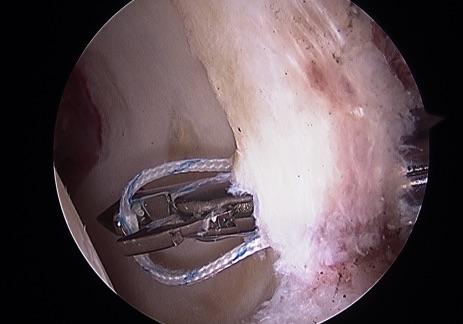

髋关节镜治疗髋臼股骨撞击综合症

"股骨髋臼撞击症"健康宣教(2):告诉您"髋关节镜手术如何治疗股骨髋臼